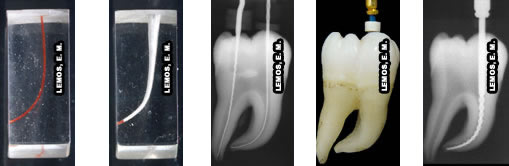

Canal Mesial Lima K # 15

Canal Mesial 30/6 – NRT